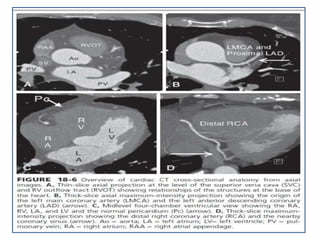

CARDIAC COMPUTED TOMOGRAPHY ANATOMY